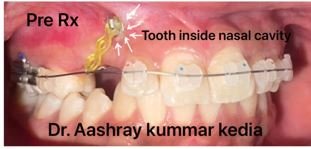

The new pioneering digital X-ray technology clinic is spear-headed by experienced dentists in Newtown, Kolkata. This equipment is specialized in customized and comprehensive one-time reports within a day for a patient so that you can easily opt for the quick diagnosis and treatment of your dental issues. This makes us the most preferred option for such query care.